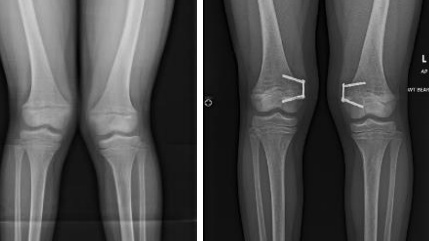

Chân chữ X (Genu valgum hay Knock knees) là tình trạng đầu gối gập vào trong, chạm nhau khi duỗi thẳng chân trong khi hai mắt cá chân vẫn cách xa nhau.

Ngoài ra, chụp X – quang là phương pháp chẩn đoán hình ảnh có thể sử dụng để kiểm tra mức độ biến dạng chân trẻ bằng cách đo góc của trục Hông – Đầu gối – Mắt cá chân. Bình thường, góc này dao động từ 1.0° đến 1.5° ở người lớn bình thường.